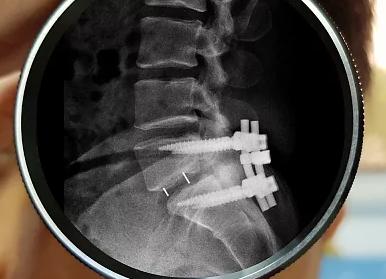

Рис.: ламинэктомия — удаление дужки позвонка

Очень часто из-за недостаточной эффективности, вызванной нестабильностью, декомпрессивная ламинэктомия дополняется стабилизирующими операциями.

Стабилизирующие операции

Фиксация позвоночника после ламинэктомии. Среди специалистов есть как сторонники фиксации, так и те, кто относятся к этому методу с осторожностью.

К достоинствам дополнения ламинэктомии системами стабилизации можно отнести повышение эффективности результатов лечения. Но есть и минусы: во время установки могут возникнуть осложнения, вызванные нарушениями в соседних позвоночно-двигательных сегментах – может развиться болезнь «смежного уровня» (спондилолистез, перелом, сколиоз).

Система межостистой фиксации основывается на обеспечении низкого уровня нагрузки на опорные задние столбы и расширение площади самого позвоночного канала.

Для того чтобы установить систему межостистой динамической фиксации, проводится задняя декомпрессия, а в затем в межостистый промежуток внедряется имплант.

Данный имплант приводит в рабочее состояние заднюю опорную колонну позвоночника и оставляет возможность разгибать и сгибать оперируемый сегмент, а также смежные ему сегменты.

Самым эффективным методом оперативной хирургии по проблеме стеноза позвоночного столба (по статистике) считают совмещение микрохирургической декомпрессии и динамической межостистой стабилизации.